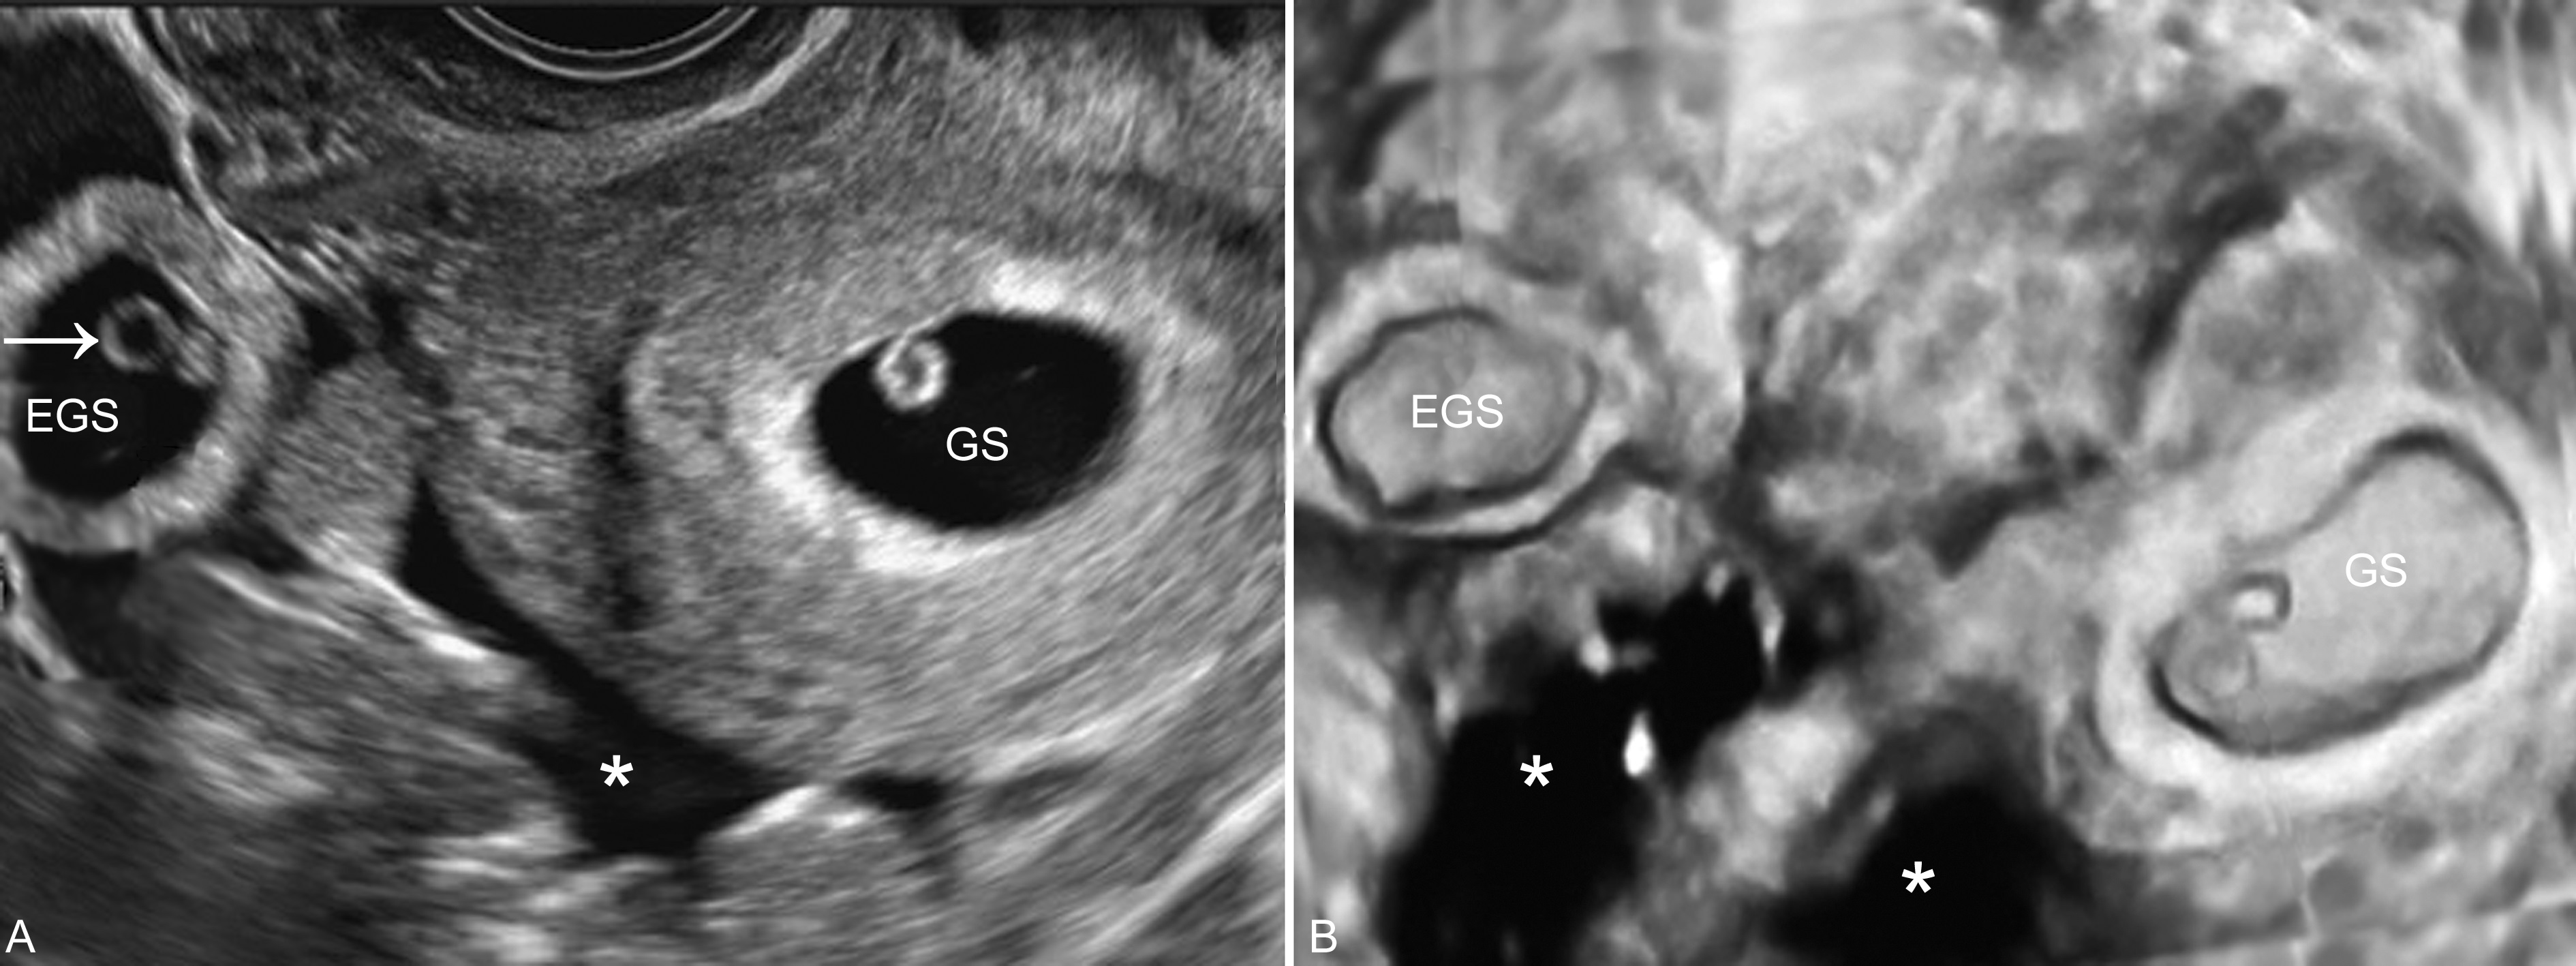

图7宫内妊娠合并宫外孕腹腔积血

1、子宫增大 在激素的作用下,几乎所有的输卵管妊娠均可引起子宫体积的增大,但大多数小于停经月份;子宫内膜回声增厚,约有10%~20%的患者宫腔内可显示梭形或扁圆形无回声结构(图1,2),称为“假妊娠囊”(false gestational sac)或称为宫腔内积液(intrauterine fluid with ectopic pregnancy)。一般认为,正常的宫内孕囊多位于子宫腔内的一侧,与子宫腔一起形成“双环征”。仔细检查其内部有无卵黄囊及胚胎回声对鉴别宫腔内妊娠和宫腔外妊娠很有价值。部分病人子宫可无明显增大。由于近年来子宫内外同时妊娠的发生率明显增加,当在子宫腔内确定妊娠后,也要仔细检查子宫旁回声,以排除子宫内外同时妊娠的可能。

3、腹腔积液 输卵管妊娠流产或破裂急性发作时,可引起腹腔内的严重出血。超声检查可在盆腔及腹腔肠间显示片状无回声区(图6,图7)。部分未破裂的输卵管妊娠亦可由于绒毛侵蚀输卵管壁、局部血管出血沿输卵管远端流出,以至有一半以上的未破裂或未流产的输卵管妊娠中也有盆腔内少量积液存在。